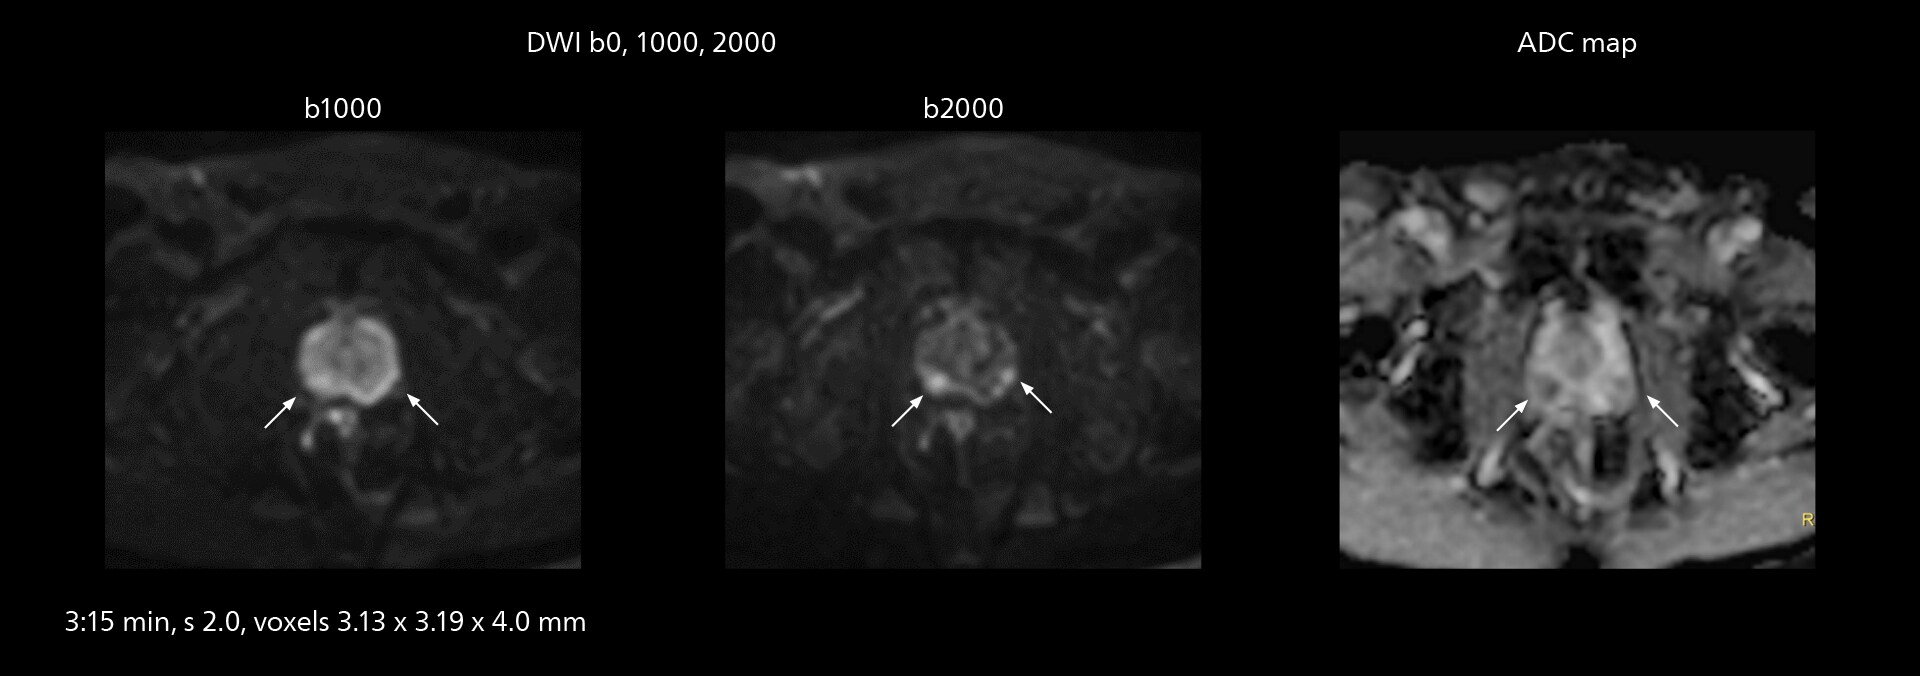

Diffusion studies benefit from powerful gradients

The high performance of the Vega HP gradients is particularly impressive in DWI. “The Vega HP gradients enable us to scan faster and use b-values as high as 2000, for example in prostate DWI and in DWIBS, which provides image quality that is remarkably improved over the previous system and we are able to more easily see lesions.”

Clinical case example: MRI of prostate

Examples of prostate imaging showing faster scan times and improved resolution illustrate the power of SmartPath to Elition X in this case of prostate cancer with PI-RADS score 4.

Prostate MRI showing cancer with PI-RADS score 4